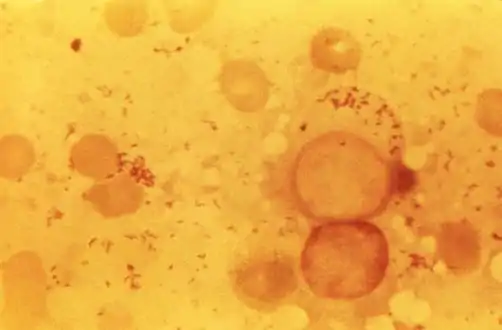

Photomicrograph of numerous, Gram-negative, Coxiella burnetii bacteria

Photomicrograph of numerous, Gram-negative, Coxiella burnetii bacteria C. burnetii, the Q fever-causing agent